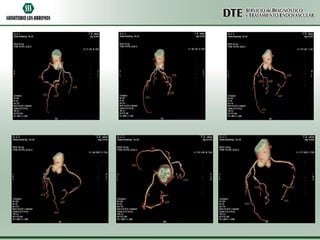

TAC MS

03-07-13